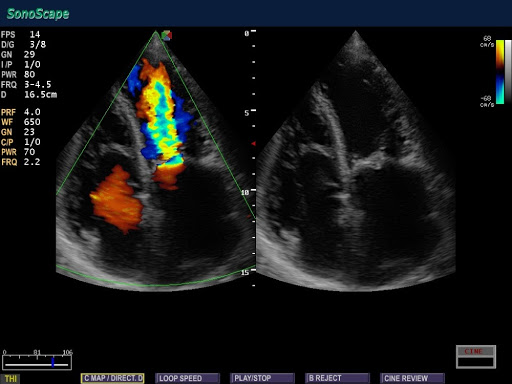

- цветной допплер Flow

- улучшенный цветной допплер eFlow

- Кардиология

Кардиология (сердце) в Flow цветном режиме |

PISA объём регургитации, толщина миокарда, профиль кровотока (опция) |